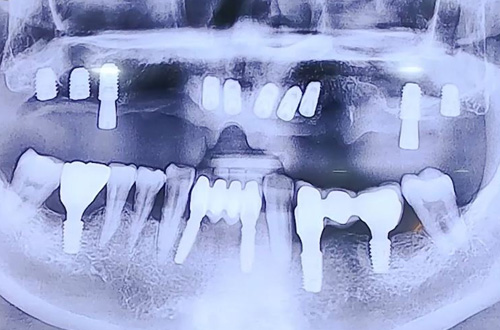

윗니 전체 임플란트 사례

22-11-23 더365치과

치료 유형 전체 임플란트

위 앞니의 브릿지 보철이 길게 사용된 상태에서,

윗니가 거의 빠지기 직전인 심각한 상태로 내원하신 환자분입니다.

따라서 당일 윗니 전체 임플란트를 진행하시고

임시틀니까지 바로 만들어 치아의 형태를 가지고 귀가하실 수 있도록 하는 것을 목표했는데요.

임플란트를 위해 기존 치아를 빼면서 즉시 본원의 3D 스캐너 트리오스로 스캔 후 본을 뜨고

그 정보를 기공소로 전달해 임플란트 치료 중 실시간으로 틀니가 제작되도록 할 수 있답니다 ^^

윗니 전체 임플란트 후 예쁘게 제작된 임시틀니까지 장착해 마무리해 드렸는데요.

추후 임플란트가 충분히 굳고 나면 최종 보철로 완성해 드릴 계획입니다.